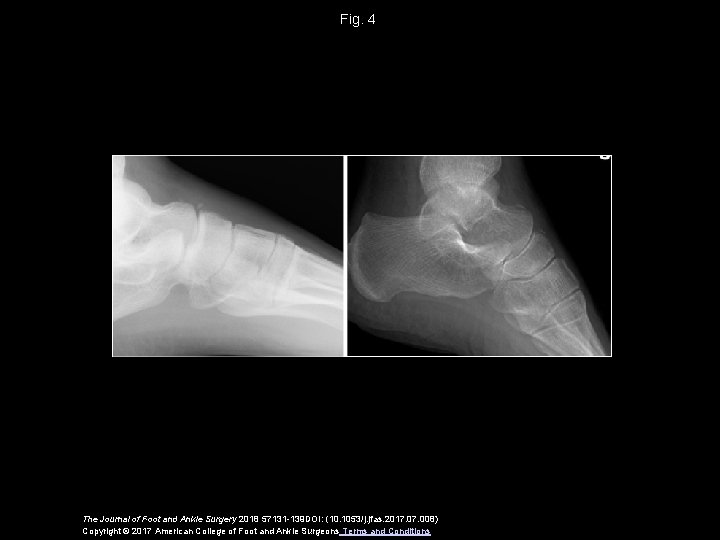

Fig. 4 The Journal of Foot and Ankle Surgery 2018 57131 -139 DOI: (10. 1053/j. jfas. 2017. 008) Copyright © 2017 American College of Foot and Ankle Surgeons Terms and Conditions